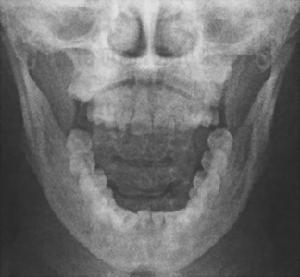

查體:觸診扁桃體區可捫到堅硬條索狀或刺狀突起,患者可訴此處為不適之處,並可誘致咽痛或咽痛加重。多為單側過長。莖突X線片常顯示其長度過長,或有偏斜、彎曲等情況。

④凡年齡在20 歲以上,如有單側或雙側咽部疼痛、異物感,伴頸部、耳部、頭部疼痛時,應詳細詢問病史,必要時行莖突X 線檢查,以除外該病;